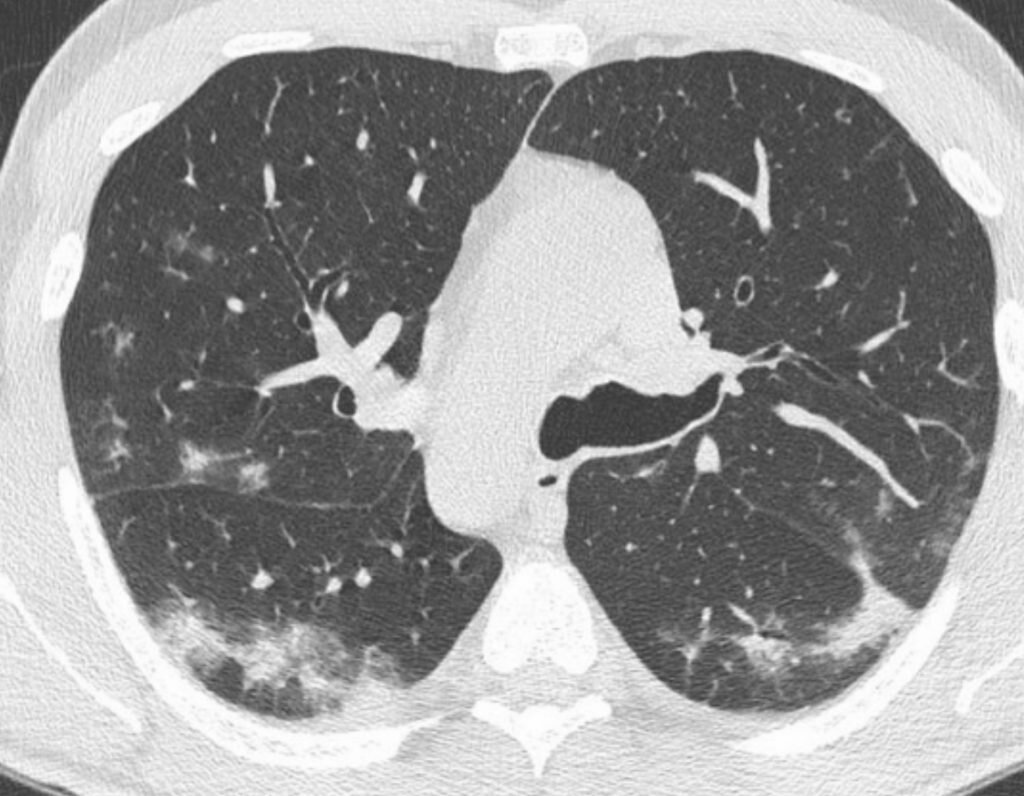

Но выявление у больного обширного поражения лёгких (более 80% поражения лёгких), которое на КТ определяется как множественные участки инфильтрации легочной ткани по типу «матового стекла», расположенные диффузно в легочной паренхиме обоих лёгких, является неблагоприятным прогностическим фактором и большим риском необходимости госпитализации в ОРИТ с назначением кислорода или переводом на ИВЛ.